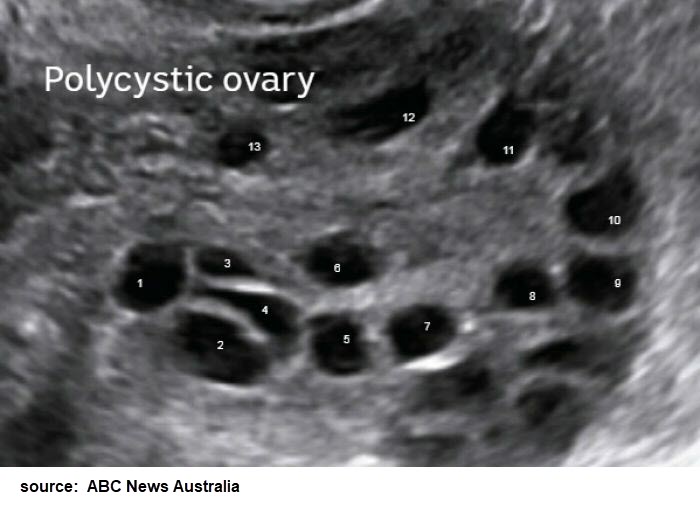

The combination clomiphnemetformin is superior to clomiphne alone as a primary method for ovulation induction and to achieve pregnancy in PCOS. Liraglutide Saxenda Victoza for PCOS. Polycystic ovarian syndrome PCOS leads to a multitude of clinical and biochemical alterations in patientsMetformin and the thiazolidenediones TZDs--which have insulin.